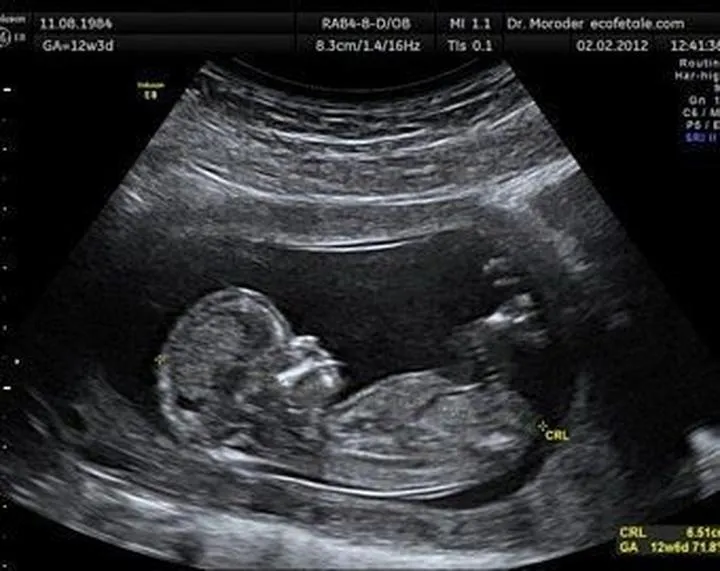

Gdy już zgubimy się w zawirowaniach dat, wówczas przychodzi czas na badanie USG, które uznaje się za znacznie dokładniejsze. Specjaliści wykonujący ultrasonografię zmierzą długość ciemieniowo-siedzeniową płodu, znaną jako CRL. To właśnie wcześniejsze USG pozwala na zminimalizowanie błędów. W idealnym scenariuszu warto przeprowadzić to badanie przed 10. tygodniem ciąży, gdy maluchy rosną w dość jednolitym tempie. Jednak jak to zwykle bywa, im później wykonasz USG, tym więcej problemów, ponieważ każde dziecko może rozwijać się w różnym tempie. Możemy zauważyć, że jedno dziecko znajduje się na innym etapie rozwoju niż drugie. Dlatego lekarze porównują dane z USG z datą miesiączki, co niejednokrotnie wywołuje zawrót głowy u przyszłych mam.

Drugim istotnym czynnikiem są dane, które lekarz analizuje. Pomiar długości ciemieniowo-siedzeniowej (CRL) stanowi klucz do oszacowania wieku płodu na początku ciąży, jednak w miarę jak maluszek rośnie, zaczynają mieć znaczenie inne parametry, takie jak dwuciemieniowy wymiar główki (BPD) czy długość kości udowej (FL). Oczywiście można się dziwić, że im więcej maluchy rosną, tym więcej parametrów trzeba mierzyć! W tym momencie wkrada się mały chaos, ponieważ niektóre dzieci mogą mieć długie nogi, podczas gdy inne mogą nieco odstawać od normy. Te różnice mogą prowadzić do tzw. „spóźnionych” pomiarów, co z kolei generuje nieporozumienia w określeniu terminu porodu.

W związku z tym, co na ten temat mówi nauka? Lekarze opierają swoje argumenty dotyczące USG głównie na pomiarach, takich jak długość ciemieniowo-siedzeniowa (CRL), której dokładność jest najwyższa w pierwszym trymestrze. Po tym okresie terminy porodu mogą się znacznie różnić, a tempo wzrostu płodu staje się bardziej nieprzewidywalne. Lekarze twierdzą, że jeżeli różnica nie przekracza sześciu dni, sytuacja jest w porządku. Natomiast, gdy zaczynamy rozmawiać o różnicach tygodniowych, to sprawy mogą się skomplikować. Mamusia w takiej sytuacji ma prawo czuć się zdezorientowana, lecz warto pamiętać, że przynajmniej zyskuje szansę na przedsmak bycia matką – to z pewnością ekscytujące, prawda?